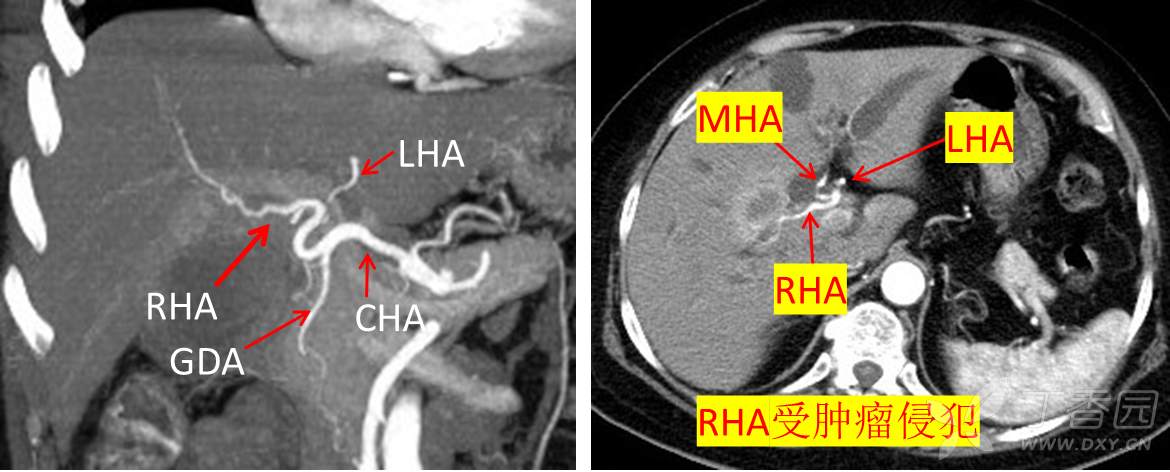

动脉评估可见右肝动脉受侵,图像如下:

门静脉右前支间隙模糊,可疑受侵,图像如下:

肝静脉评估未见异常,如下图: